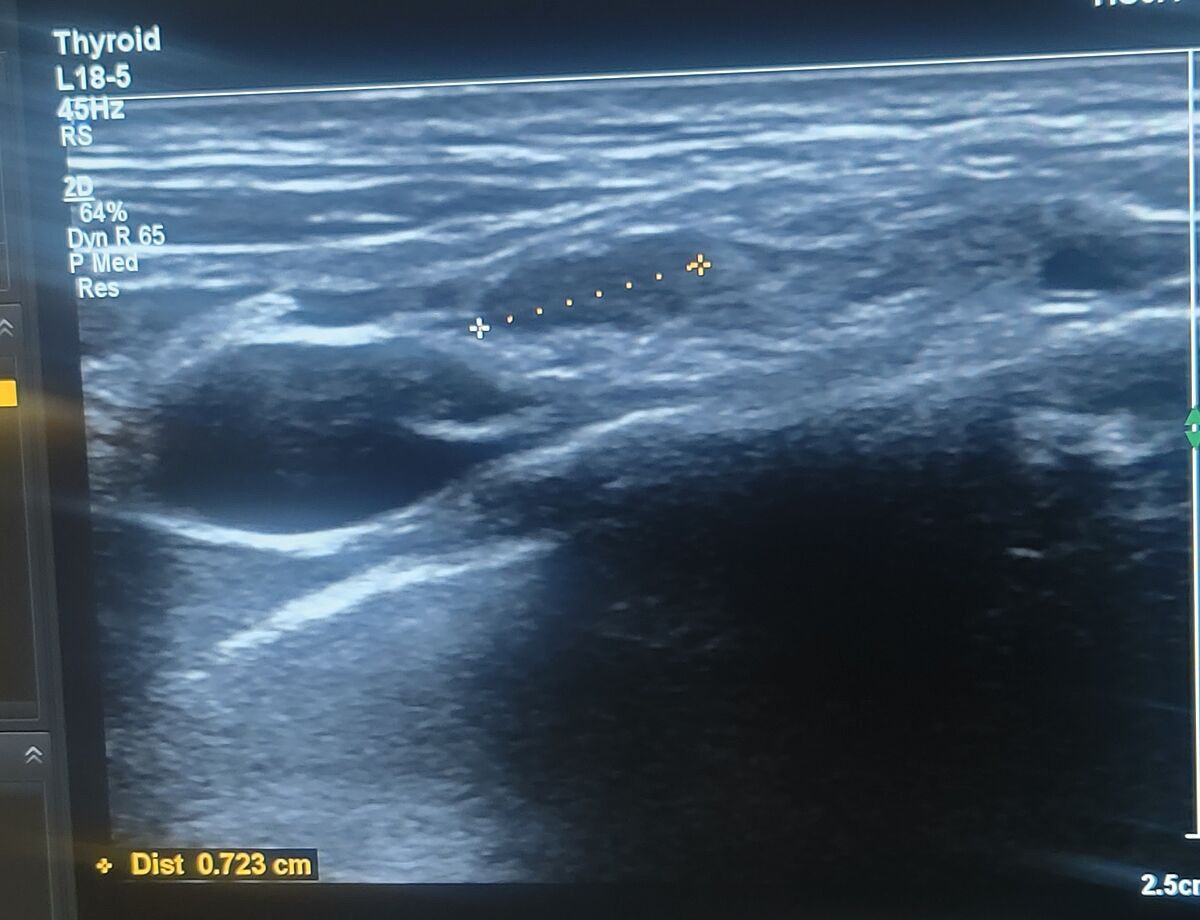

Хто розуміється на УЗД

Подиввться УЗД, яка тут структура ? Однорідна чи ні?

Ну так Узел же, не?

Цікавить структура, цей вузол два лікарі описують по різному, один з нормальною структурою, інший пише , що з неоднорідною структурою

И как описывает неоднородность второй врач? Микрокальцинаты, полости? Или что он там видит?

Узел какой? Гипоэхогенный?

Просто неоднорідної структури пише

Решта все в нормі, лише неоднорідна структура. А інший УЗД лікар дивився і каже я не бачу неоднорідної, тут все добре , однорідна структура